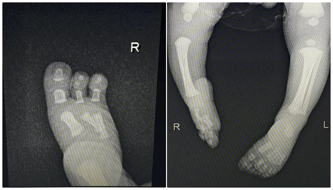

Cel zbiórki: Dwie operacje ortopedyczne, rehabilitacja

Dzięki Waszym dobrym sercom udało się zebrać środki na dwie operacje naszego dziecka. Niestety te operacje to nie koniec leczenia. Filipka czeka w przyszłości jeszcze kilka operacji i rehabilitacja, która będzie mu towarzyszyła niemalże do końca życia.

Choć przed nami jeszcze długa droga, to nigdy się nie poddamy i zrobimy wszystko, aby Filipek mógł kiedyś stanąć na równych nóżkach. ❤️